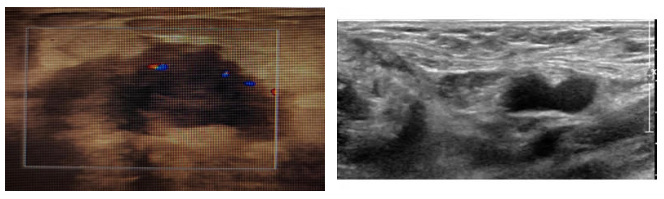

CT:提示右侧乳房未见明显的肿块,右侧腋窝淋巴结明显肿大;

图2. 胸部CT 2021.9.25